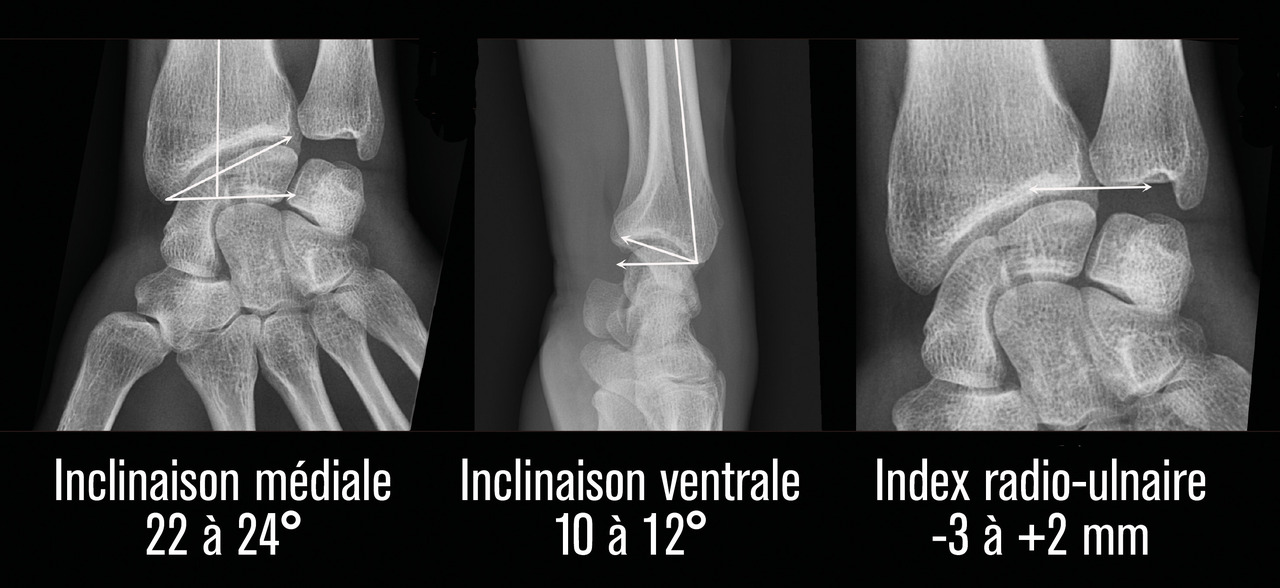

La surface articulaire distale, encroûtée de cartilage, répond au carpe distalement et présente deux facettes, scaphoïdienne et lunarienne (fig. 3), séparées par une crête de direction antéropostérieure. Cette surface articulaire a une double concavité transversale et sagittale. Il est crucial de retenir qu’elle possède une double inclinaison ventrale (10 à 12° en moyenne dans le plan sagittal) et médiale (22 à 24° en moyenne dans le plan coronal), très spécifique, qu’il faudra s’efforcer de restituer et de maintenir dans le traitement de la composante métaphysaire de ces fractures (fig. 4). L’index radio-ulnaire distal, défini par la longueur relative du radius par rapport à l’ulna, est le troisième critère morphologique à évaluer (fig. 4). Ce dernier, dont les valeurs normales sont très variables, est en moyenne neutre à 0 mm (-3 mm à +2 mm).

L’analyse précise et détaillée des clichés radiographiques renseigne sur les critères morphologiques importants détaillés plus haut : l’inclinaison frontale, l’inclinaison sagittale et l’index radio-ulnaire distal. Il faut également apprécier les caractéristiques métaphysaire et épiphysaire de la fracture et la présence de lésions associées : comminution, nombre et déplacement des fragments articulaires, fractures de l’extrémité inférieure de l’ulna, fractures des os du carpe, lésions ligamentaires intracarpiennes ou de l’articulation radio-ulnaire distale.